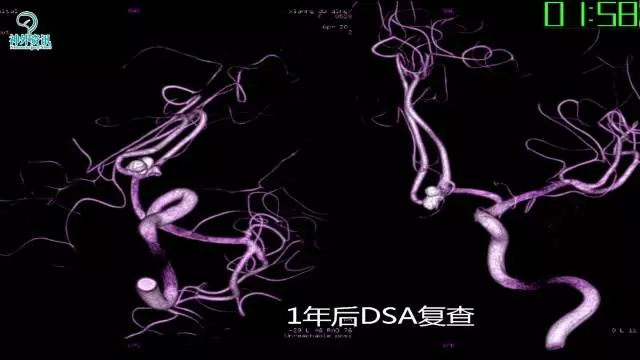

今天为大家分享的是“强生医疗CNV-神经介入专栏”第三十六期,由重庆第三军医大学附属新桥医院神经外科刘俊带来的“Galaxy弹簧圈在不规则动脉瘤中的临床应用”精彩讲课视频及PPT,欢迎观看。文章仅代表作者个人观点,如有不同见解,欢迎同道斧正!